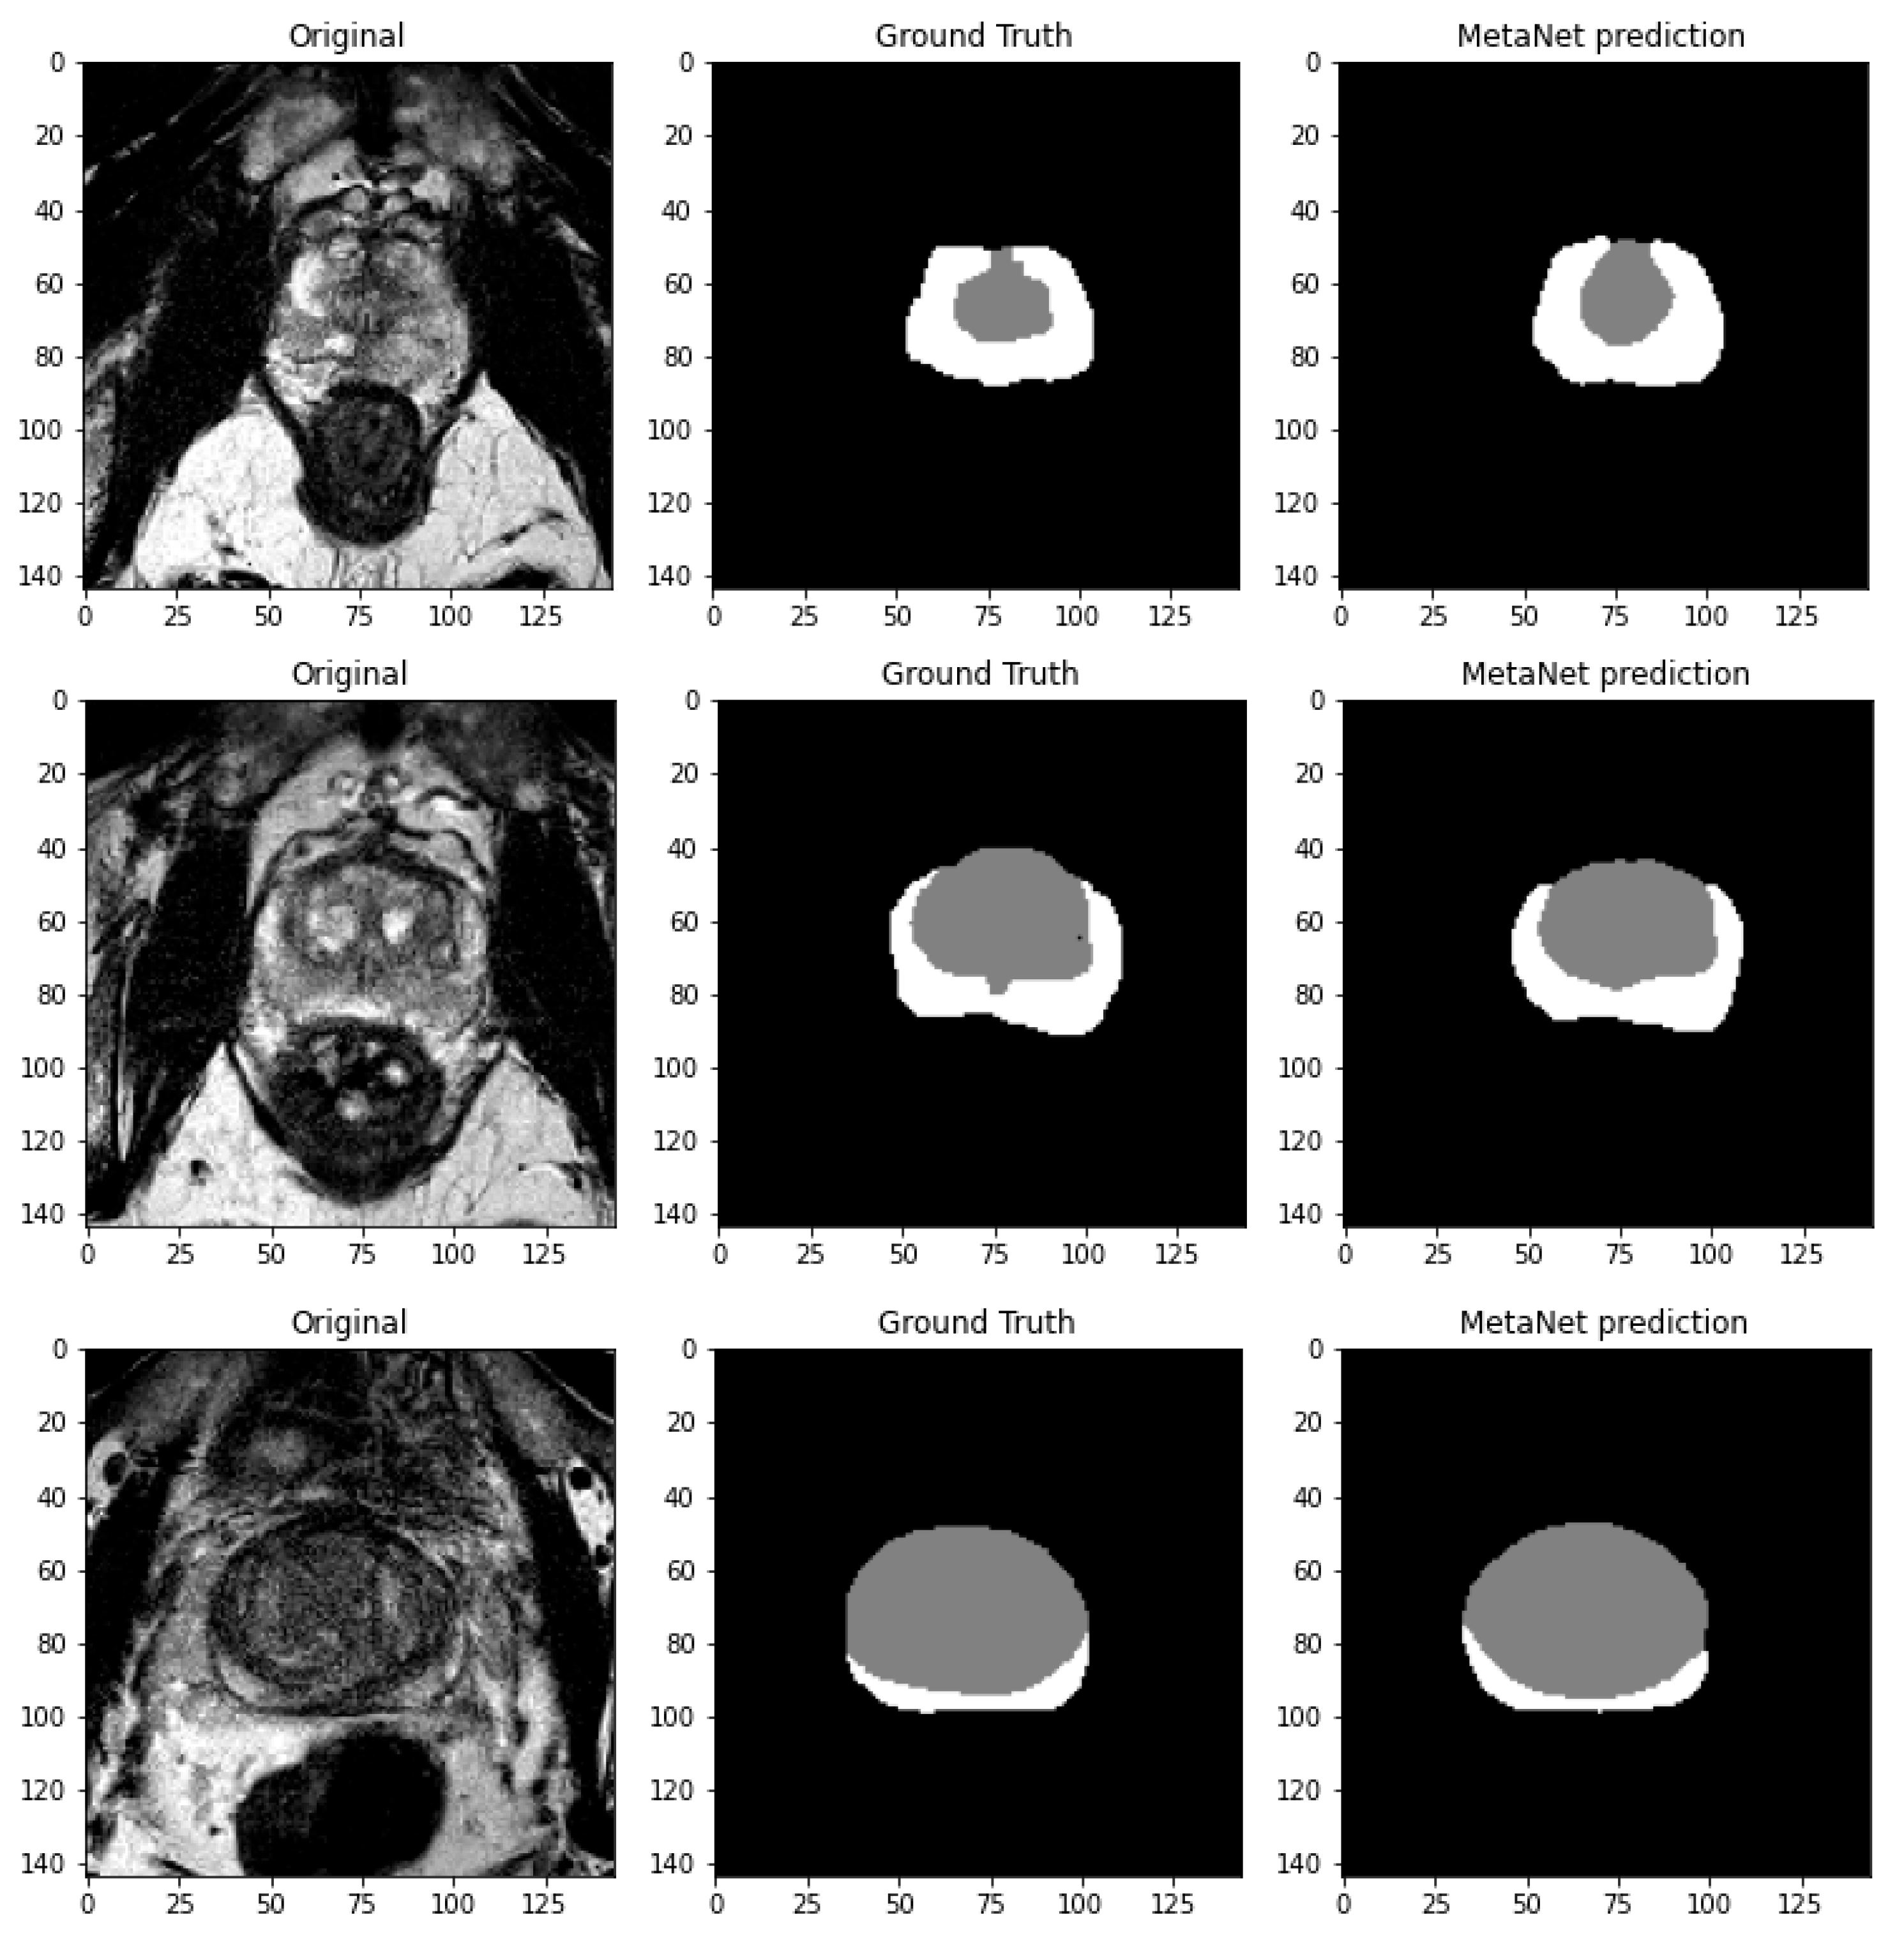

3.2.2. Meta-Net

4. Results